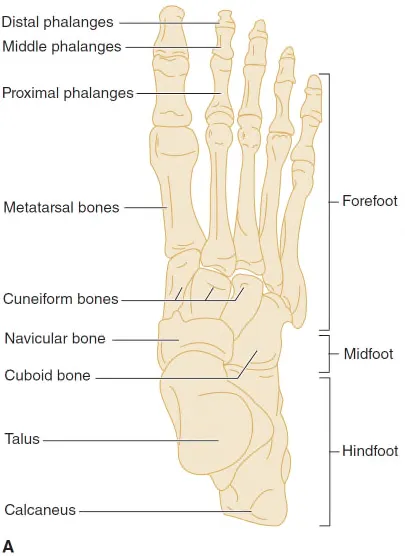

A. Anatomy

A1. Bone - 3 sections

(1) Hindfoot

Calcaneus, Talus

(2) Midfoot (Lisfranc joint)

Navicular, Cuboid, Cuneiform(medial, middle, lateral)

(3) Forefoot

Metatarsals, Phalanges(proximal, middle, distal)